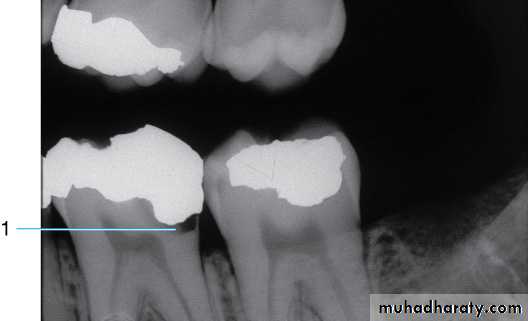

Bitewing radiograph. This radiograph shows (1) large occlusal caries, (2) radiolucent lines or mach band effect (an optical illusion caused by overlapped enamel), (3) interproximal caries, and

(4) cervical burnout